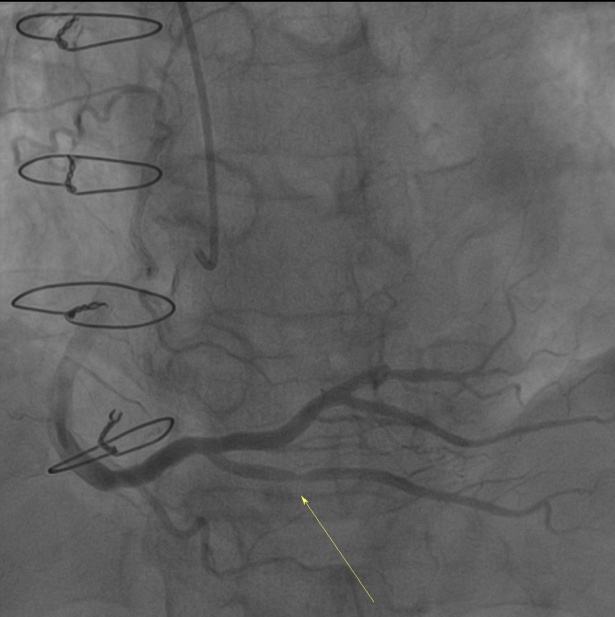

图2、3. 术前和术前测量

据悉,该患者10年前曾经行心包剥脱术,出现阵发性胸痛症状后到我院就诊,冠脉造影提示右冠状动脉狭窄80%。在详细了解情况后,心血管内科专家与影像专家进行了会诊,为患者确定了周密的治疗计划和手术方案。